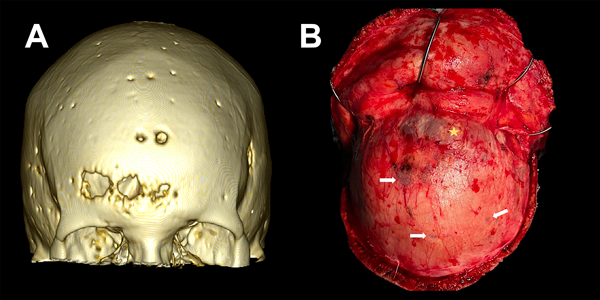

Figura 3. Lesiones osteolíticas con componente exofítico transcraneano. A) TC con reconstrucción 3D de ventana ósea donde se evidencia calota erosionada por lesiones en sacabocado, características del mieloma múltiple. B) Correlación intraquirúrgica de lesión osteolítica y exofitica (estrella amarilla). Presencia de múltiples lesiones en sacabocado a nivel de la calota craneana (flechas blancas).